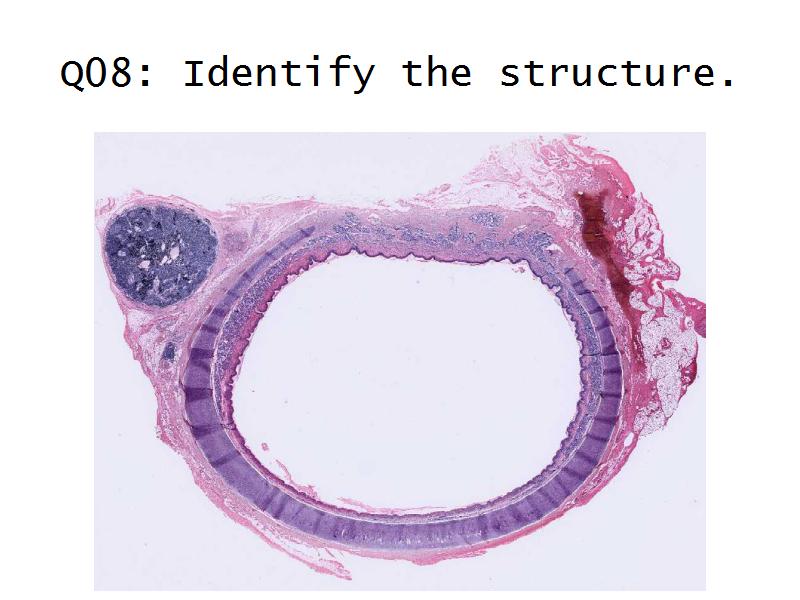

Slides 28 & 76

- Basic anatomy of the kidney

- Basic arrangement of nephrons and collecting tubules in the kidney

- Structure of the nephron and collecting tubules

- The renal corpuscle

- Make an annotated drawing of the macroscopic view of the kidney.

- Complete the drawings for each slide in the practical workbook.